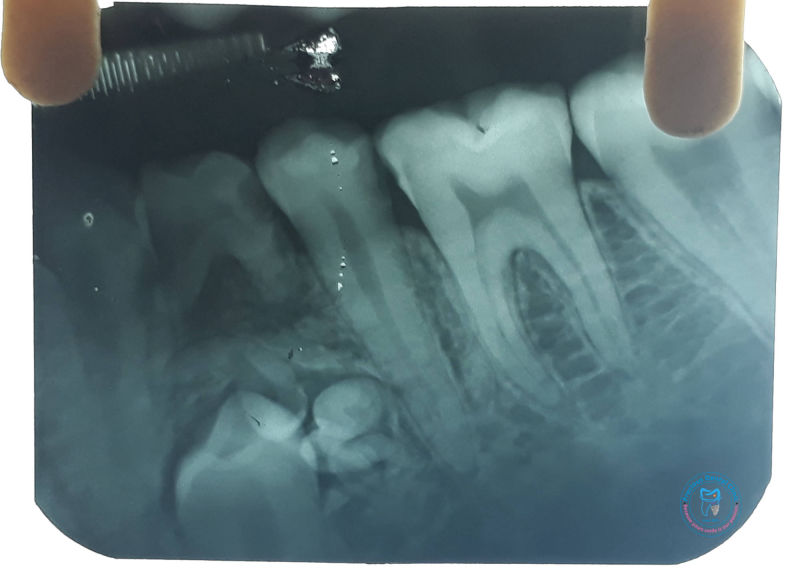

Collection of photos, here you will find the photos of doctor, services, environment and work.